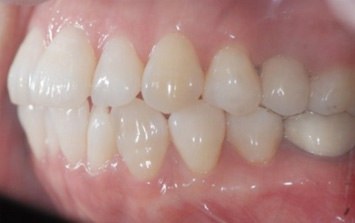

왼쪽 어금니 상실로 내원한 환자분. 어금니 임플란트의 경우 씹는 기능이 중요하기 때문에 저작능력 회복이 가장 중요합니다.

임플란트를 식립하고 강한 자극과 힘에 견딜 수 있도록 튼튼한 지르코니아 보철물로 수복하였습니다.

지르코니아는 인공 다이아몬드 재질로 강도가 우수합니다. 강한 교합력에 저항성이 강한 동시에 도자기의 심미적 장점을 함께 가져

어금니에 적합한 보철물 입니다.